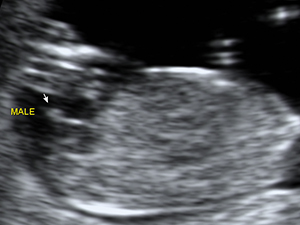

懷孕12週的男性胎兒性 器官(箭咀)